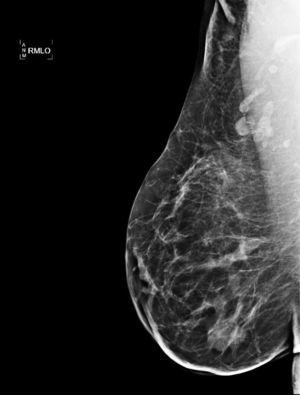

Caso clínicoMujer de 38 años, que acude a urgencias de nuestro hospital el 14 de octubre del 2010 por presentar un proceso inflamatorio, supurativo y doloroso en el cuadrante supero-externo de la mama derecha. Entre de sus antecedentes familiares, encontramos hermana con cáncer de mama. Antecedentes personales ginecoobstétricos: gestaciones 3; abortos uno; partos 2, con última gestación hace 5 años; anticoncepción con preservativo; el resto, sin interés. En la exploración, se aprecia todo el cuadrante supero-externo de la mama derecha eritematoso, caliente y con un punto de drenaje a piel, por lo que se piensa en una mastitis aguda y se inicia tratamiento con cloxacilina 500mg cada 6 h durante 7 días, estreptoquinasa 40mg cada 12 h y analgesia. Cuatro días después, se evidencia un empeoramiento del cuadro, objetivándose una masa de 6cm de diámetro y pezón derecho umbilicado y adenopatías axilares de tamaño patológico. Se cambia el tratamiento antibiótico por amoxicilina-clavulánico 875/125 cada 8 h durante una semana y se solicitan mamografía y ecografía mamaria (figs. 1 y 2). Por las características del proceso, se piensa en un cuadro inflamatorio/infeccioso, con un área de probable caseificación o en un carcinoma inflamatorio.

Mamografía: se observa un aumento difuso de la radiodensidad, con claro incremento de la trabeculación, preferentemente a nivel de los cuadrantes externos, más focalizada en el cuadrante supero-externo. También afecta al plano cutáneo, preferentemente a nivel del complejo aréola-pezón, el cual engrosa y retrae.

La mamografía, la ecografía y la RMN son usadas principalmente para excluir malignidad más que para diagnosticar la mastitis granulomatosa, ya que las imágenes obtenidas no son específicas. La mamografía puede darnos signos indistinguibles de un carcinoma. La ecografía nos puede mostrar una imagen hipoecogénica e irregular con sombra posterior o con la presencia de zonas tubulares. La RMN puede ser útil en la evaluación de la extensión de la lesión y en la evolución. Puede mostrar hipodensidad central, hiperintensidad periférica, lesión heterogénea o una lesión circunscrita con captación heterogénea del contraste2-9.